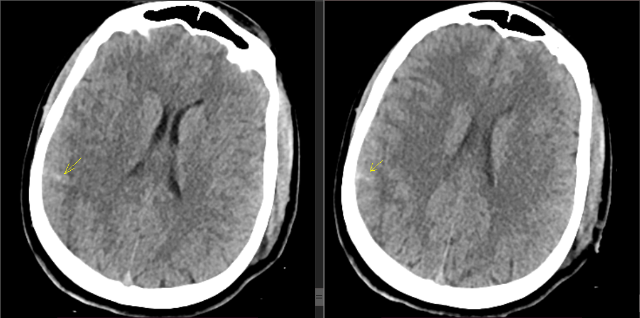

Есть очаги в головном мозге